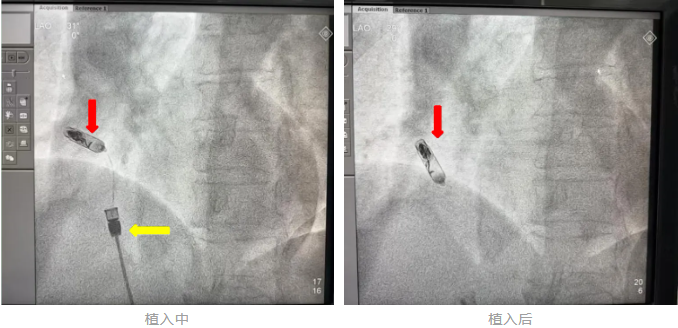

螺旋锚定:通过DSA影像引导,将起搏器的双螺旋电极精准旋入右心耳基底部,多角度X线透视确认位置稳固;

注:红色箭头为无导线起搏器,黄色为递送系统术中影像